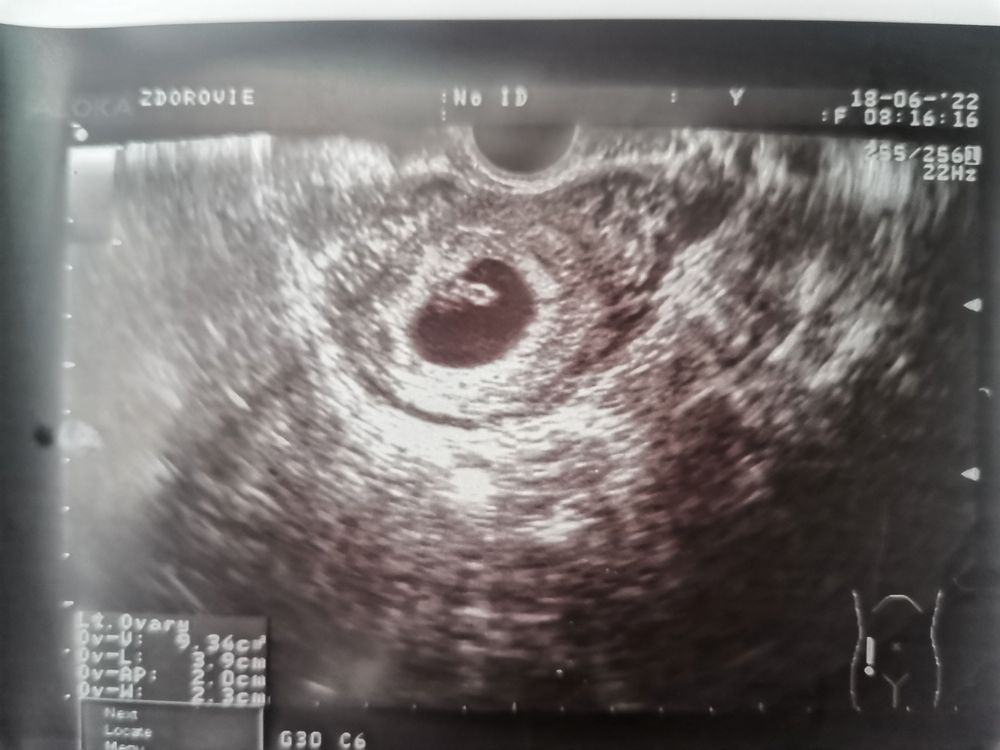

УЗИ 6 нед. 6 дн. Увидели все, что нужно! 🥰

Срок по месячным 7 нед. 2 дн., по овуляции и УЗИ - 6 нед. 6 дн.

ПЯ - 21 мм. КТР - 9 мм. ЖМ - 4 мм. СБ - 120 уд./мин.

Врач сказала, что все показатели идеальные, - как по учебнику😊 Никаких отслоек и гематом, тонус матки в норме. Нет ни одного повода для волнения. Как же я рада!!!